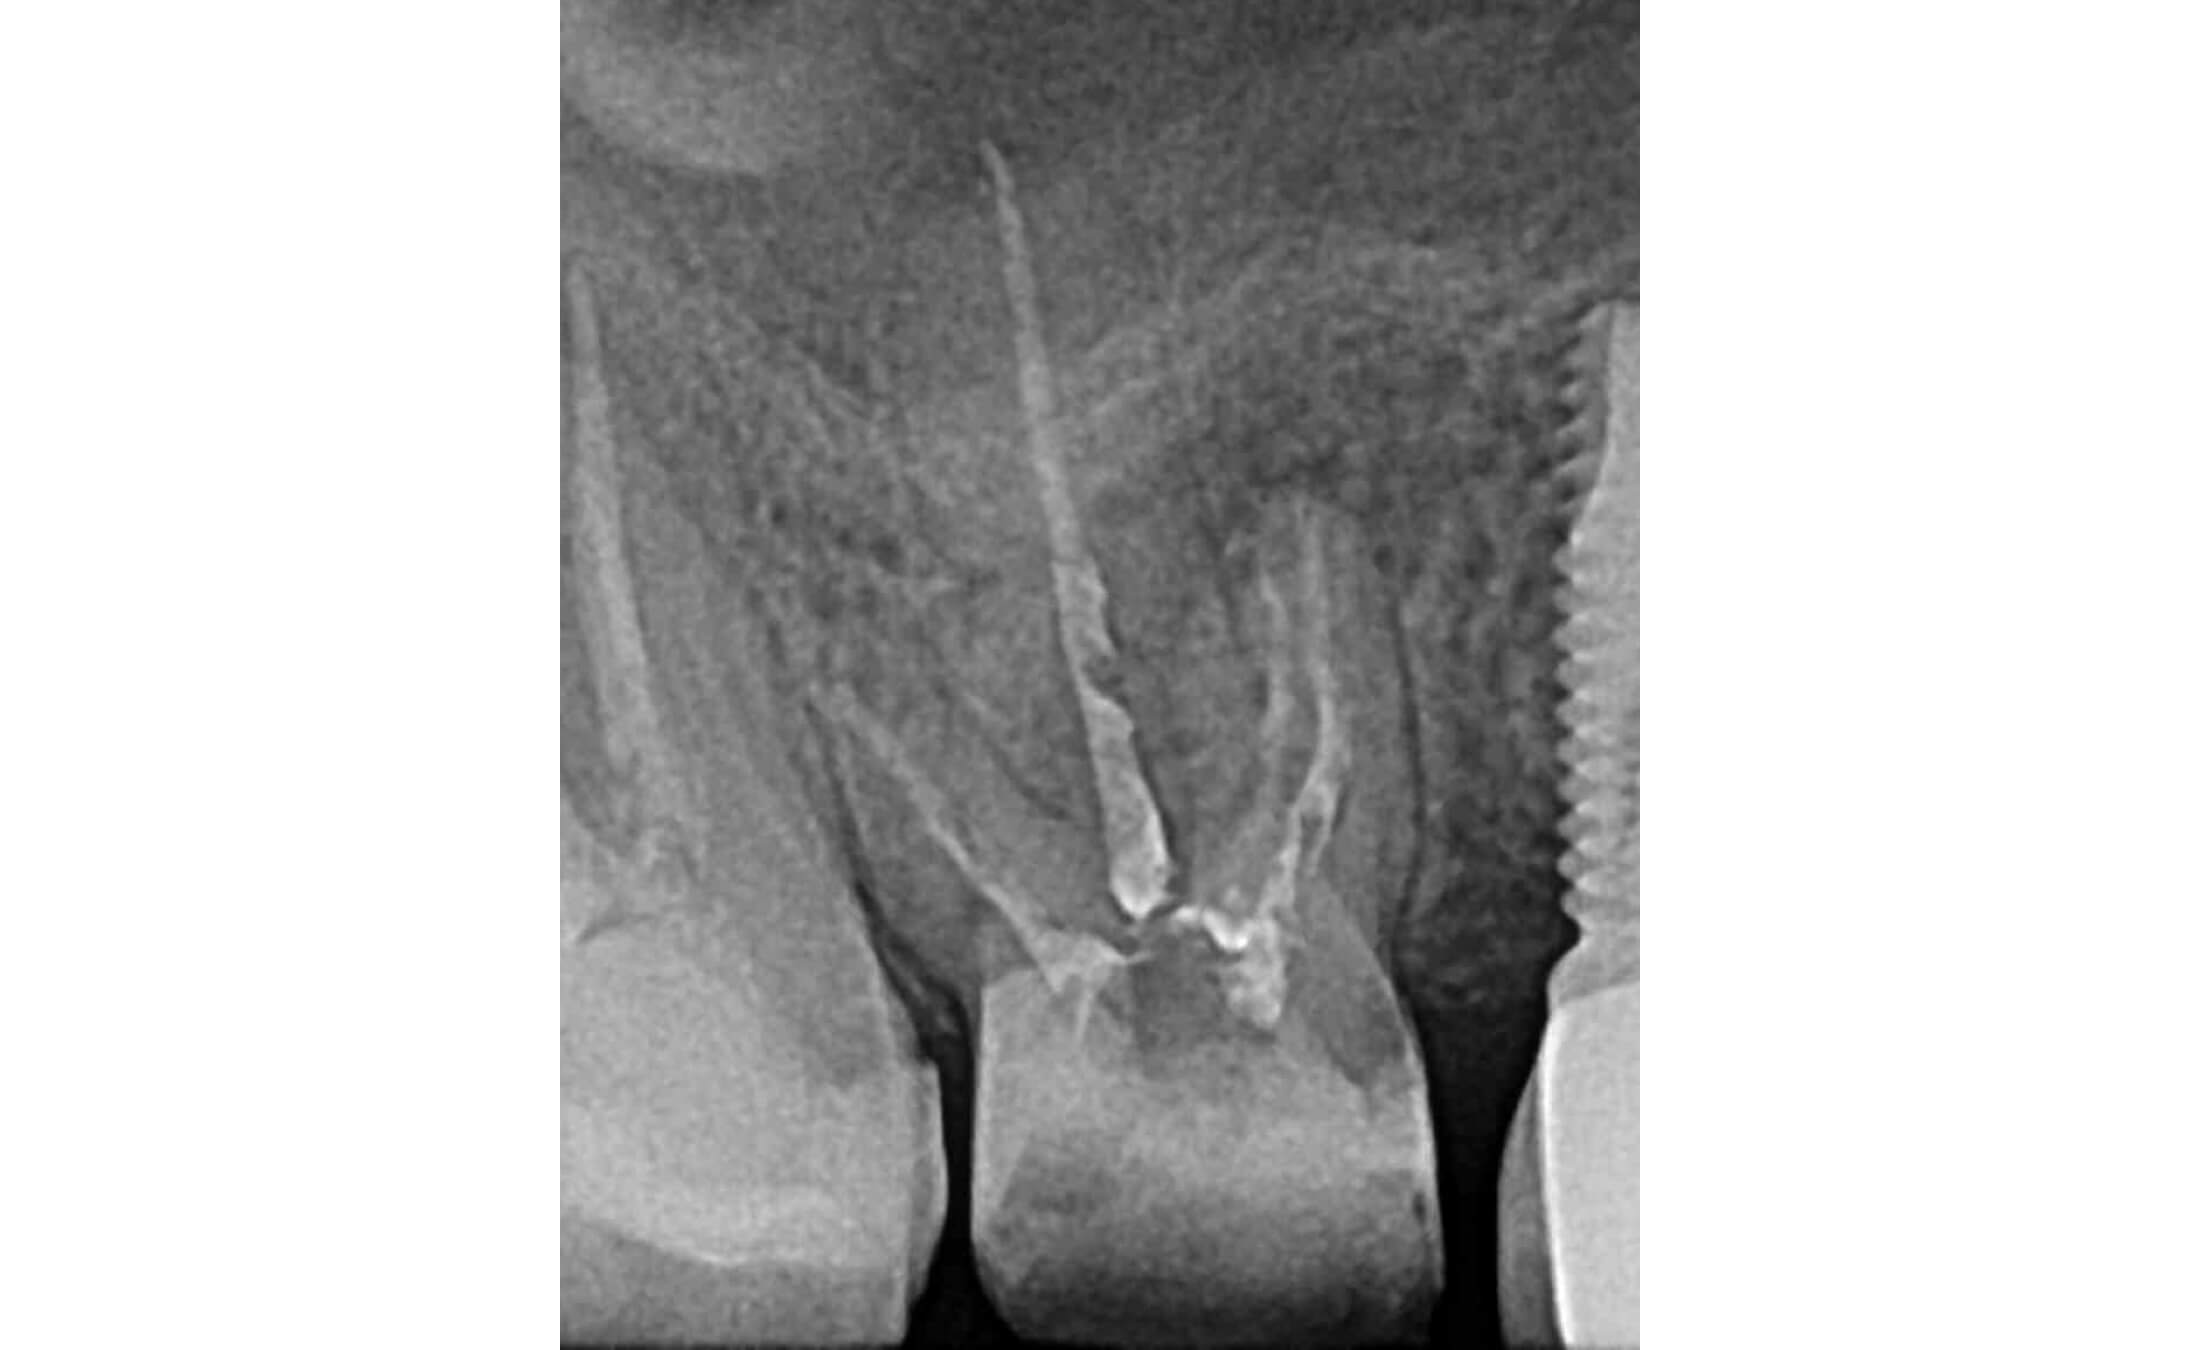

1. Исходная ситуация, зуб 16, апикальный периодонтит, обширная зона перирадикулярной деструкции в области передне-щечного корня, свищевой ход. (Фото 1-4)